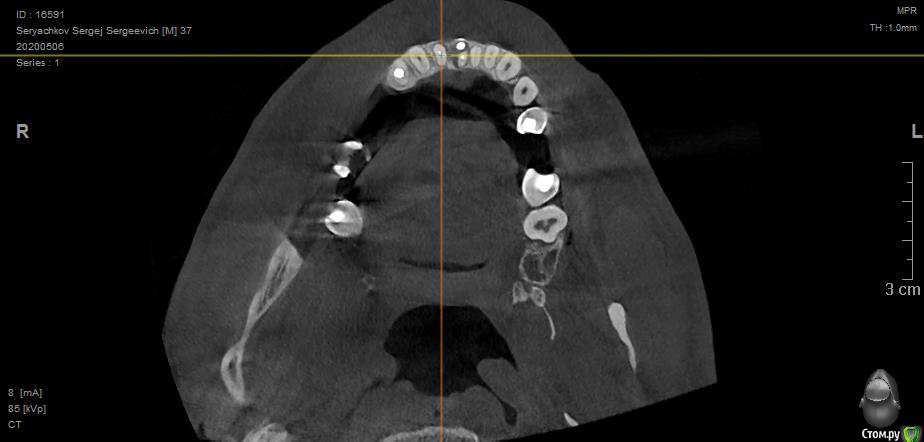

Под передними резцами обнаружилась обширная киста. В трёх клиниках предложили различное решение, но все основаны на удалении двух зубов, под которыми киста. Есть ли вариант сохранить и полечить зубы или удаление неизбежно?